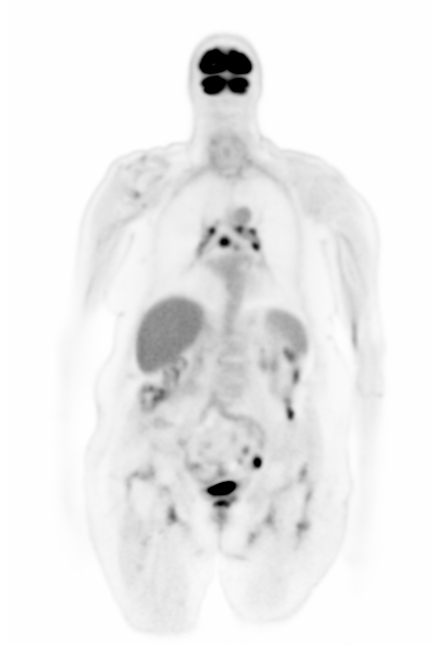

In this section, we present the results of our \acFDG-trained \acDLSE model applied to \acPSMA to evaluate its ability to generalise to radiotracers not included in the training data.

Figure 9 shows two clinical \acPSMA dataset examples. The first dataset illustrates a patient with a prostate lesion and shows good agreement between the \acDLSE and \acSSS corrected \acPET images for both the organs and the lesion.

The second patient example features two adjacent liver lesions; one with a higher and one with a lower activiy level compared to the background liver activity. The \acDLSE-corrected image shows higher activity levels in both the liver and the lesions. Based on a \ac3D manual segmentation of the liver and the FLAB segmentation of the lesions, the contrast values were found to be similar for \acDLSE and \acSSS, with values of and , respectively, for the necrotising lesion, and and , respectively, for the active lesion. These values compare with contrasts of and , respectively, in the non-scatter-corrected image.

Finally, Figure 9 shows visually similar results between \acDLSE and \acSSS-corrected images. Furthermore, \acSUVmax values were found to be similar between the two methods (Figure 10). These results suggest that the method could adapt from one radiopharmaceutical to another without the need for retraining.